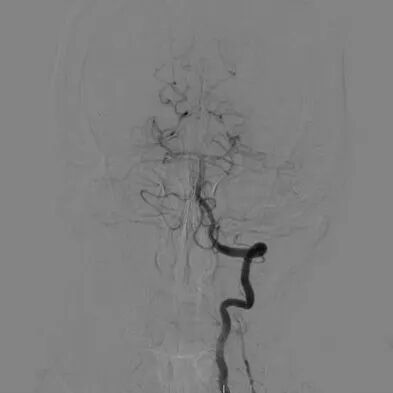

心脑联合造影

-- 右侧颈内起始部中度狭窄,经前交通向左侧代偿